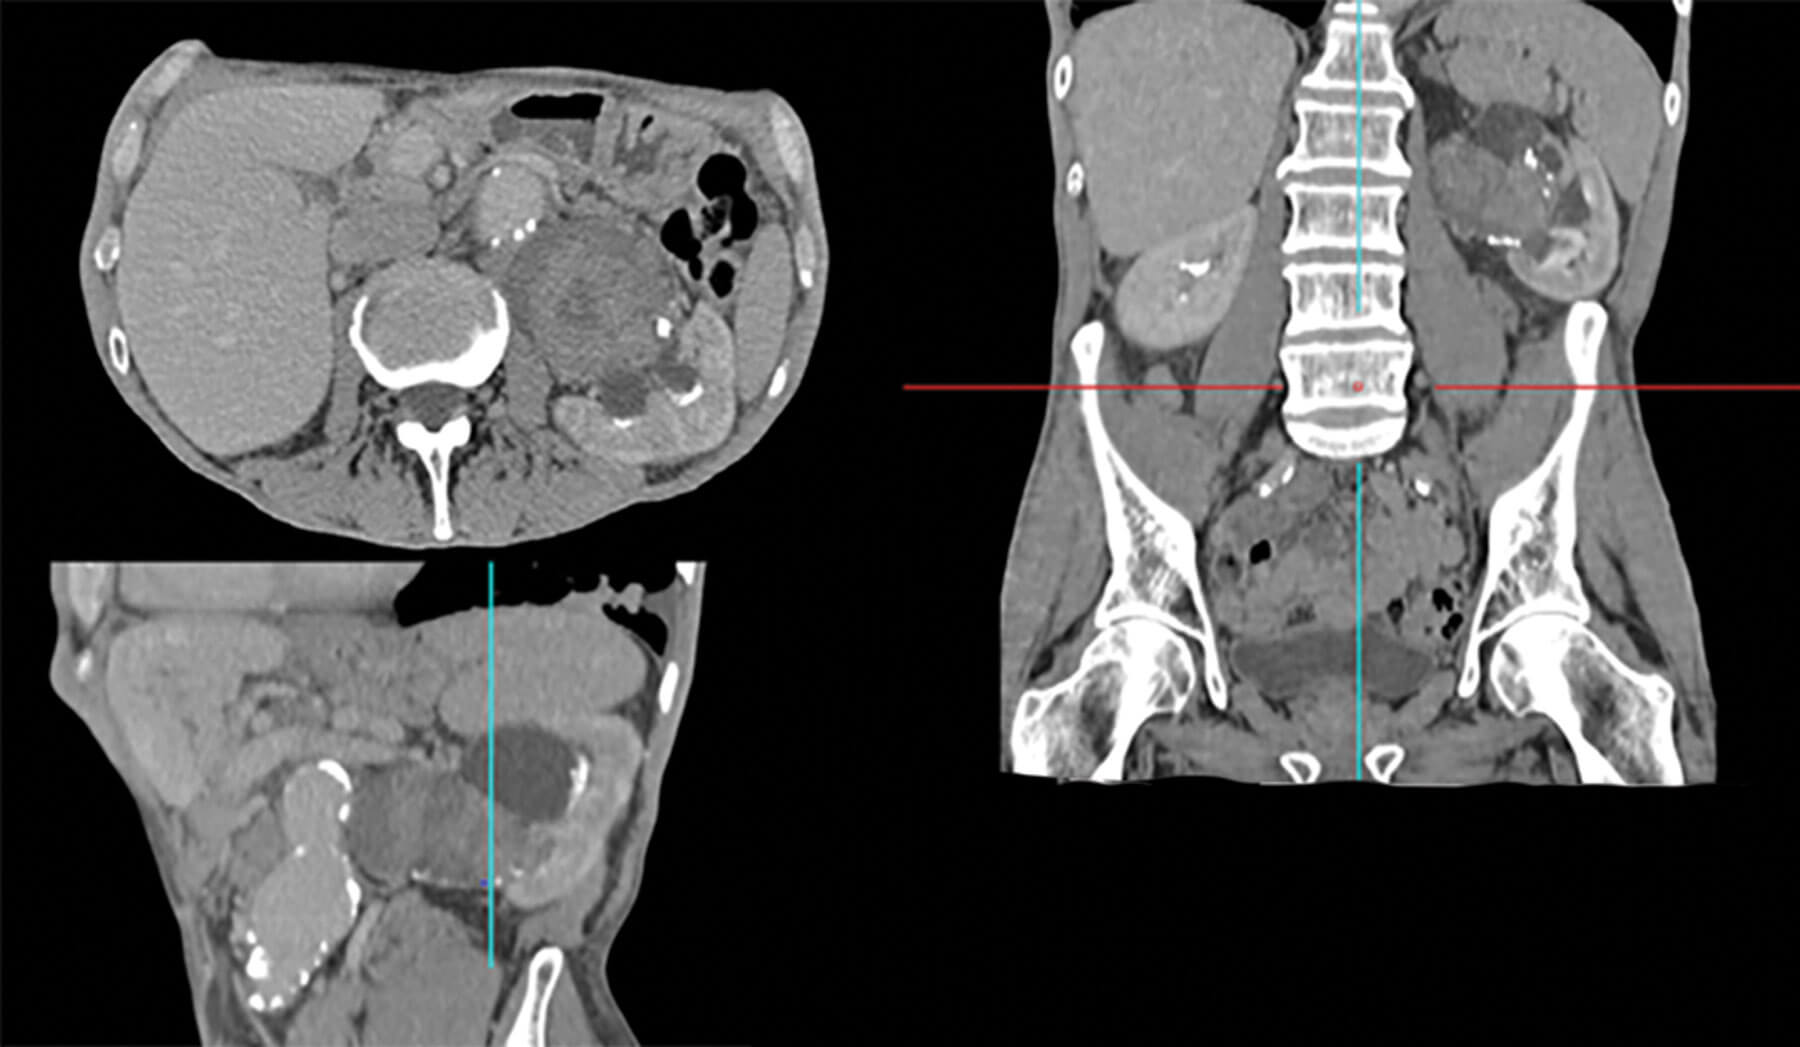

CT urography remains the gold standard imaging for diagnosing UTUC. Through creation of a 3D construction of the urinary system any abnormalities of the urothelium caused by UTUC, shown by filling defects, can be assessed [8].

The European Association of Urology (EAU) recommend CT imaging during the urographic phase as it has been shown to be the most efficacious modality for the diagnosis of UTUC, with meta-analyses assessing the sensitivity and specificity demonstrating 92% and 95%, respectively [8]. CT urography is also necessary to enable staging of extramural disease progression to best guide overall management of the patient.

Figure 1: Reconstructed CT scan in urographic phase showing a large UTUC in the renal pelvis. This image also highlights the surgical challenge that can be present in such cases like the associated aortic aneurysm anterior to the UTUC. A reconstructed image is important in planning the treatment.